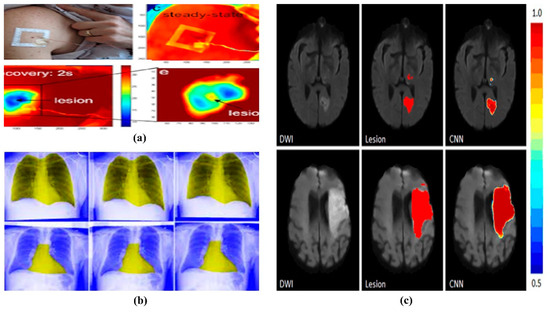

However, with the advancement in imaging technologies comes the challenge of managing and interpreting vast amounts of medical data. Despite the proliferation of imaging modalities, there is a pronounced shortage of specialized radiologists. This disparity has highlighted the potential of artificial intelligence (AI), specifically deep learning (DL), to fill the gap. DL, especially its subset known as convolutional neural networks (CNNs), excels in analyzing medical images, acting as an effective tool for pattern recognition and diagnosis [6,7,8,9,10]. DL applications on medical data are visualized in Figure 1.

Figure 1.

(a). Identifying skin cancer lesions [11]. (b). Enlarged heart [12]. (c). Acute brain stroke [13].